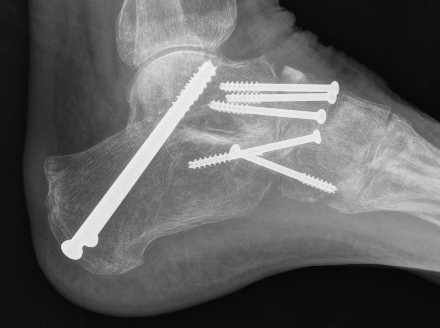

Medial displacement calcaneal osteotomy

Technique

Lateral approach

- curve just below peroneals

- protect sural nerve branches

- homann superiorly in front of tendoachilles

- homann inferiorly under calcaneum

Oblique osteotomy behind posterior facet

- 45o cut with saw

- open with lamina spreader

- split periosteum medially with osteotome

- avoid damage to medial structures

- transfer medially 1 cm

- screw fixation